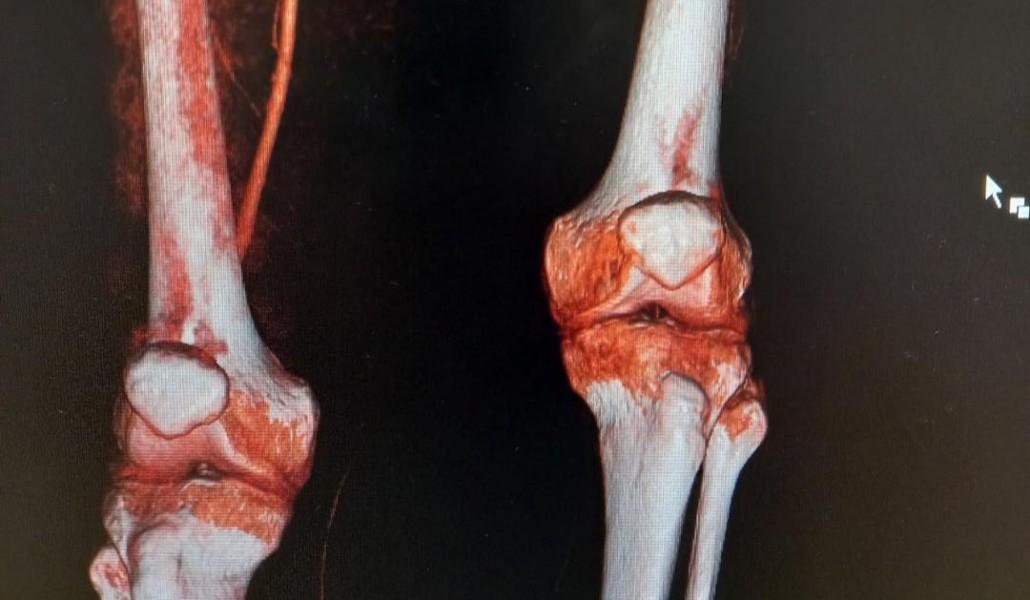

Բժիշկ անոթաբան Ռաֆայել Մանվելյանի կողմից օրերս «Բեսթ Լայֆ» ԲԿ-ում կատարվել է մի հետաքրքիր վիրահատություն։

Պացիենտը` 59 տարեկան տղամարդ, դիմել է ձախ ստորին վերջույթի սուր ցավերի կապակցությամբ , ինչպես նաև ոտնաթաթի և սրունքի շրջանում արդեն առկա զգացողականության կորստի և շարջումների մասնակի կորստի կապակցությամբ։

Հիվանդի մոտ ախտորոշվել է ստորին վերջույթի զարկերակների սուր խցանում(սուր իշեմիա 2B , որը սպառնում էր ձախ վերջույթի փտախտով:

Կատարվել է ներանոթային բալոնային դիլատացիա, ինչպես նաև թրոմբէկտոմիա և սրունքի ֆասցիոտոմիա:

Արդյունքում հաջողվել է պահպանել վերջույթը և վերացնել ցավերը: